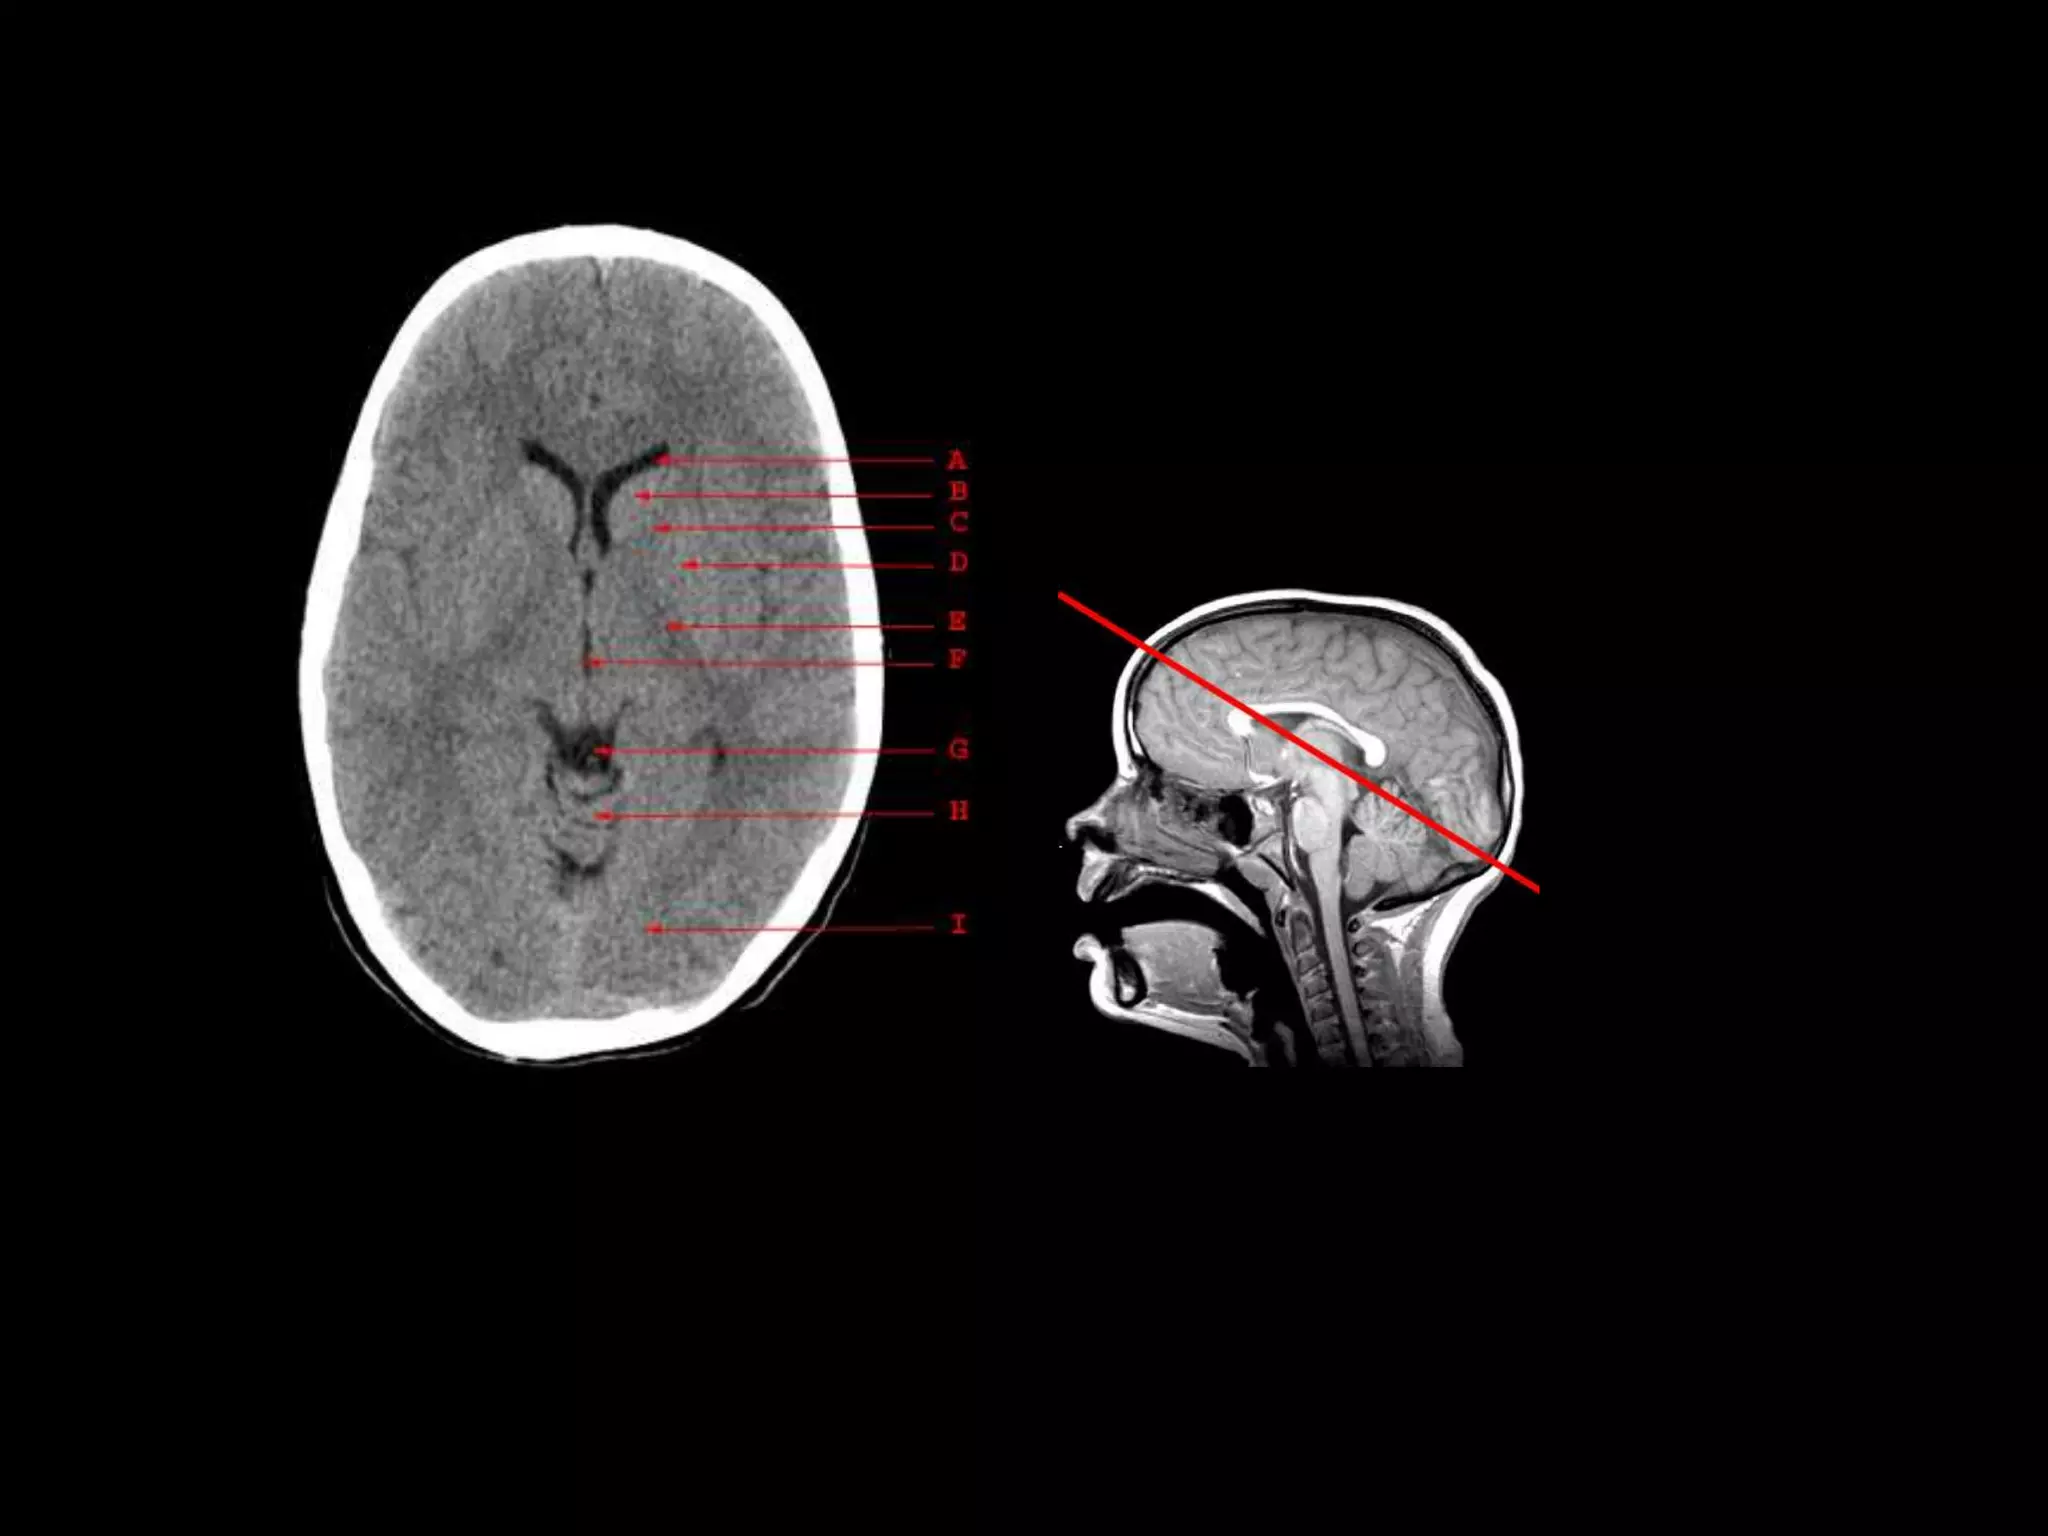

A. Anterior Horn of the Lateral Ventricle

B. Caudate Nucleus

C. Anterior Limb of the Internal Capsule

D. Putamen and Globus Pallidus

E. Posterior Limb of the Internal Capsule

F. Third Ventricle

G. Quadrigeminal Plate Cistern

H. Cerebellar Vermis

I. Occipital Lobe

Used with permission University of Virginia Health Sciences Center